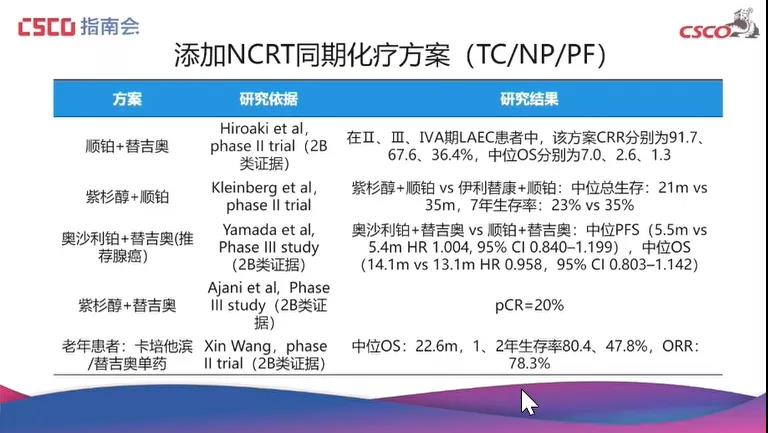

食管癌非手术治疗的化疗模式探索赵快乐教授:美国肿瘤放射治疗协助组(Radiation Therapy Oncology Group,RTOG)设计的RTOG850...